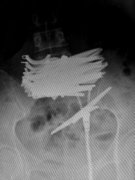

女子吸毒后吞下近10把剪刀(图)

2015-05-14 09:31:00

红网长沙5月14日讯(潇湘晨报记者杜方江)5月13日上午,42岁的曲颖(化名)躺在省直中医院普外科的病床上。前一天晚上,其因腹痛被路人发现后拨打120,送往医院救治。X光片显示,其中下腹部横亘着一捆剪刀,曲颖称自己为了躲避被抓 ... [详细]